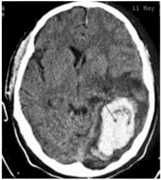

Surgery is usually indicated in the following scenarios:

- Large clots in the frontal, temporal or occipital regions with progressive clinical deterioration (Figure 4).

Figure 4: L. temporal occipital clot with mass effect, pre and post surgery

Left temporal-occipital clot with mass effect

After surgery, good recovery